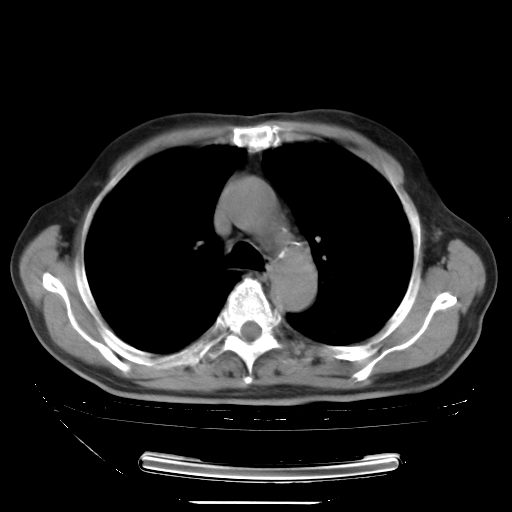

胸腹部CT,诊断意见:左上肺叶钙化灶、左侧胸膜局限性增厚并钙化、胆囊炎。描述部分肺组织呈磨玻璃样改变。